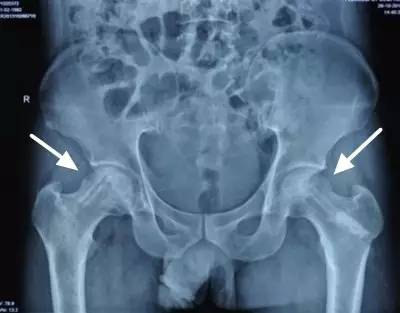

股骨头坏死的诊断

股骨头坏死的治疗效果与病情轻重、发现早晚、病程分期有很大关系,病变发现越早,病情越轻,治疗效果就越好,因此股骨头坏死应做到早期诊断和早期治疗。髋 关节核磁共振、髋关节CT以及同位素骨显像等影像学检查虽然价格较X线片贵,但是往往可以帮助医师更早地发现股骨头坏死。